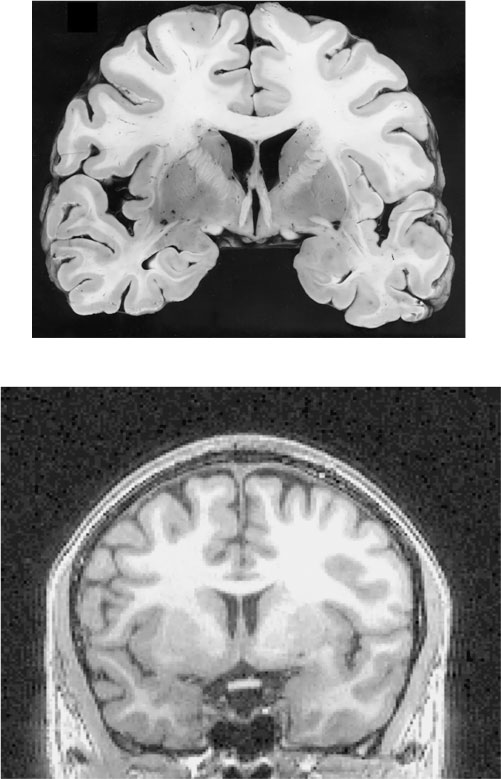

Рис. п.1. Общий вид и срез головного мозга человека

Человеческий мозг, вид сбоку (вверху). Стрелкой отмечено место, где прошел срез, показанный на нижней фотографии. Наружный слой мозга (кора) состоит из серого вещества и образует множество складок, позволяющих уместить большу́ю площадь поверхности в малом объеме. Кора содержит порядка 10 миллиардов нервных клеток.

Рис. п.2. Пример полученного с помощью МРТ структурного изображения мозга и срез мозга, извлеченного из трупа

Вверху – фотография одного из срезов мозга, извлеченного из черепа после смерти и нарезанного тонкими слоями. Внизу – изображение одного из слоев мозга живого человека, полученное методом магнитно-резонансной томографии (МРТ).